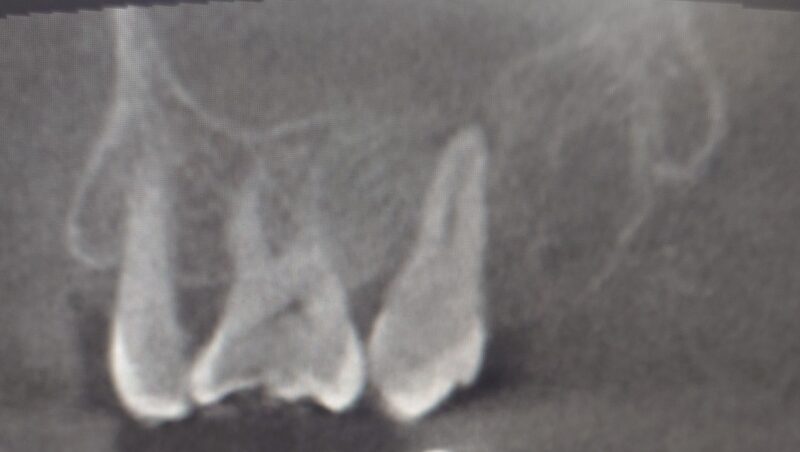

術前 一番奥の歯の根の先に影 上顎洞内は白濁して映っています